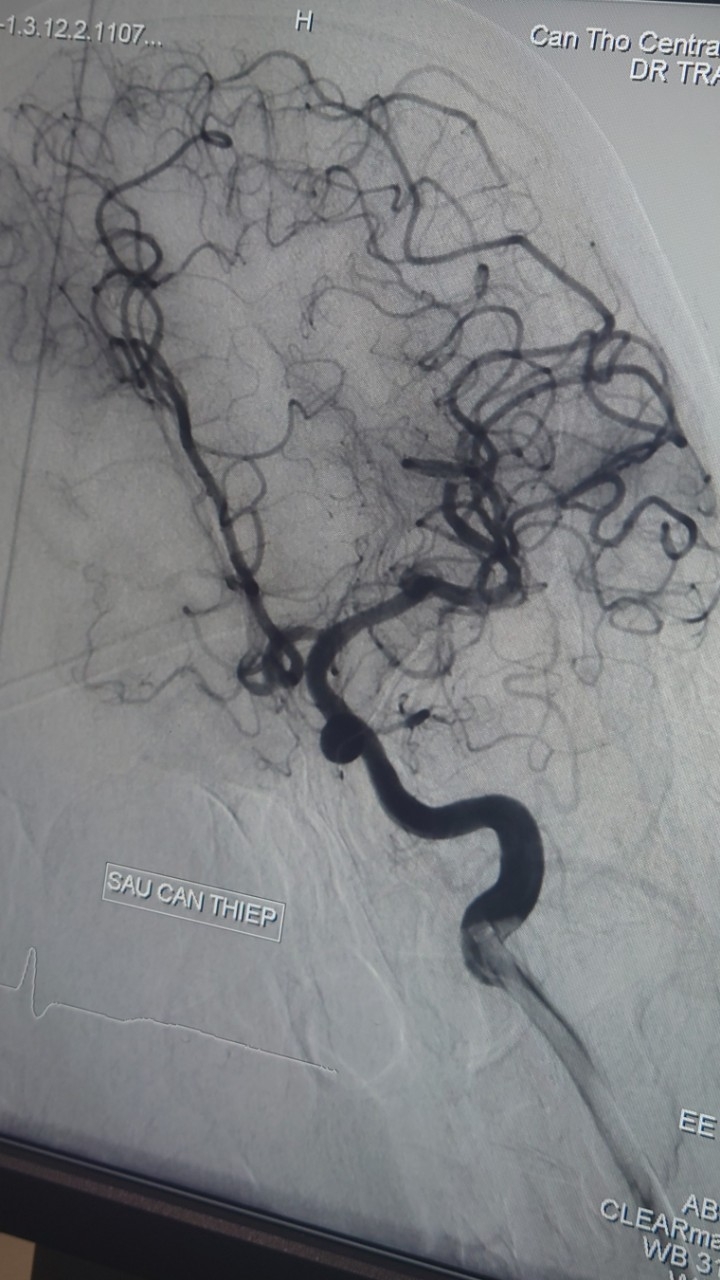

| Hình ảnh chụp mạch máu số hóa nền (DSA) động mạch cảnh trong trái (sau can thiệp) |

Ê kíp can thiệp mạch não do TS.BS Hà Tấn Đức, BS Trịnh Thành Tín thực hiện. Quá trình can thiệp, ê-kíp hút ra rất nhiều huyết khối, kết quả tái thông hoàn toàn mạch máu bị tắc, toàn bộ quá trình can thiệp lấy huyết khối là 45 phút.